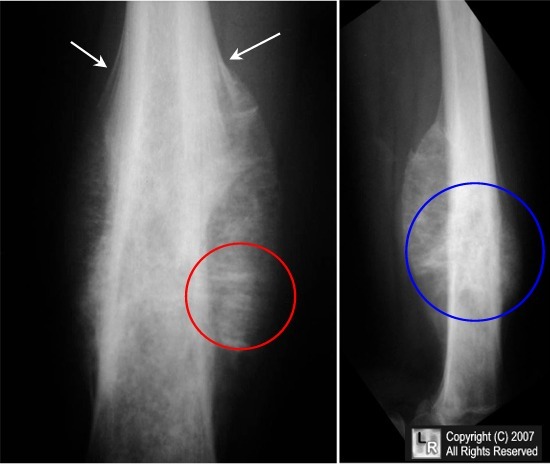

what is the radiological appearance of Ewings sarcoma

onion skin

where do Ewings sarcomas tend to occur

along long bones